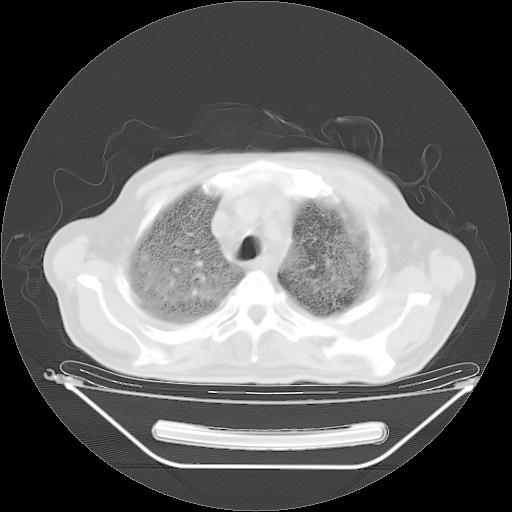

今天复查肺部CT,发现双肺广泛磨玻璃样改变。所以我把3月19日和5月9日相隔50天的肺部CT上传。请大家会诊。

5月9日肺部CT(在4月27日齐鲁医院肺部CT描述部分肺组织磨玻璃样改变,12天后肺组织广泛磨玻璃样改变)

2009年5月9日肺部CT

大致读了系列胸部CT:纵隔窗无明显异常,肺窗:从4、27至今:主要是双肺中下野外带可见毛玻璃样改变,目前处于急性肺泡炎阶段,至于原因考虑1、结替组织或胶原血管性疾病所致?2、恶性疾病如恶组在肺部所致的表现或细支气管肺泡癌?3、药物或其它原因如肺蛋白沉着症所致肺泡炎目前不太可能?总之,明天就去请我院的呼吸科、感染科、血液科和临免专家会诊哈。